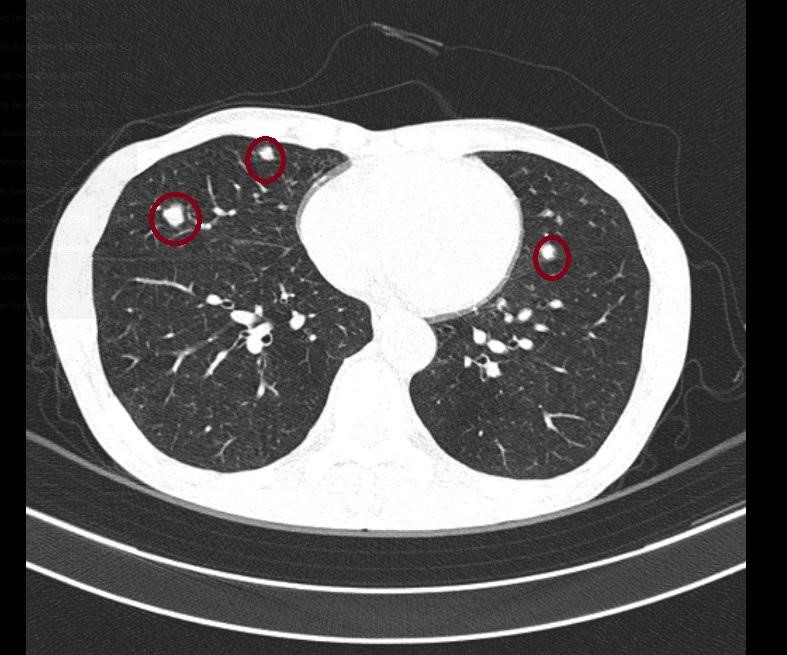

Chụp CT lồng ngực:

|

Hình 3:Hình ảnh chụp CLVT

Hình ảnh các nốt đặc, bờ không đều, đường kính lớn nhất 10mm ở 2 bên phổi